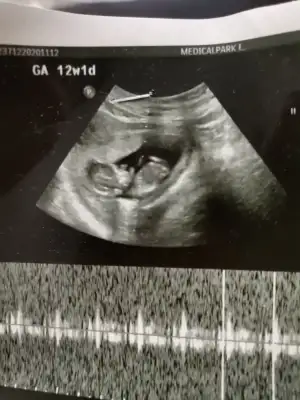

Cinsiyet tahmini yapabilirmisin kizlar 12 haftalik fotoda

• IMG_20201217_013947.webp

IMG_20201217_013947.webp

34,6 KB · Görüntüleme: 79